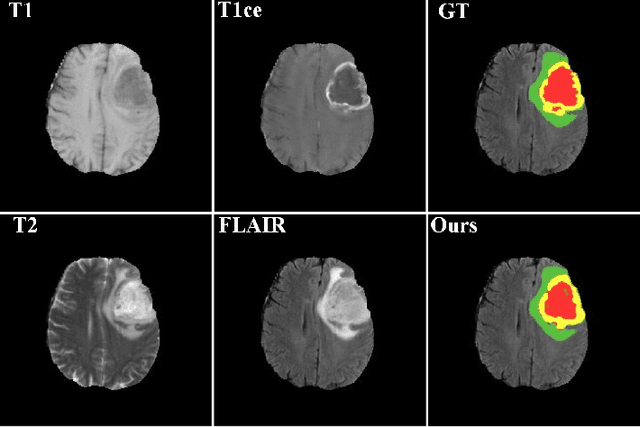

Abstract:Brain tumor segmentation is a challenging problem in medical image analysis. The goal of brain tumor segmentation is to generate accurate delineation of brain tumor regions with correctly located masks. In recent years, deep learning methods have shown very promising performance in solving various computer vision problems, such as image classification, object detection and semantic segmentation. A number of deep learning based methods have been applied to brain tumor segmentation and achieved impressive system performance. Considering state-of-the-art technologies and their performance, the purpose of this paper is to provide a comprehensive survey of recently developed deep learning based brain tumor segmentation techniques. The established works included in this survey extensively cover technical aspects such as the strengths and weaknesses of different approaches, pre- and post-processing frameworks, datasets and evaluation metrics. Finally, we conclude this survey by discussing the potential development in future research work.

Abstract:Automated segmentation of brain tumors in 3D magnetic resonance imaging plays an active role in tumor diagnosis, progression monitoring and surgery planning. Based on convolutional neural networks, especially fully convolutional networks, previous studies have shown some promising technologies for brain tumor segmentation. However, these approaches lack suitable strategies to incorporate contextual information to deal with local ambiguities, leading to unsatisfactory segmentation outcomes in challenging circumstances. In this work, we propose a novel Context-Aware Network (CANet) with a Hybrid Context Aware Feature Extractor (HCA-FE) and a Context Guided Attentive Conditional Random Field (CG-ACRF) for feature fusion. HCA-FE captures high dimensional and discriminative features with the contexts from both the convolutional space and feature interaction graphs. We adopt the powerful inference ability of probabilistic graphical models to learn hidden feature maps, and then use CG-ACRF to fuse the features of different contexts. We evaluate our proposed method on publicly accessible brain tumor segmentation datasets BRATS2017 and BRATS2018 against several state-of-the-art approaches using different segmentation metrics. The experimental results show that the proposed algorithm has better or competitive performance, compared to the standard approaches.